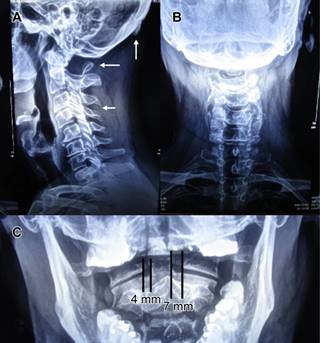

Con manifestaciones clínicas relacionadas con circulación de arterias vertebrales, se solicitaron radiografías AP, lateral y proyección transoral (Figura 1), las cuales revelaron: escoliosis cervical izquierda, inversión de la lordosis con vértice en C4-C5, anterolistesis de C4/C5 grado I, disminución de los espacios discales C3-C4 y C6-C7 por discartrosis, así como ausencia de arco posterior del atlas, con presencia sólo de tubérculo posterior, además se observa osteofito en protuberancia occipital externa. Se solicitaron radiografías dinámicas y tomografía computarizada de columna cervical, las primeras mostraron verticalización del tubérculo posterior del atlas a la flexión, y horizontalización del mismo en extensión, además de anterolistesis C4/C5 (Figura 2), la tomografía confirmó diagnóstico de anomalía congénita del atlas tipo D de la clasificación de Currarino (Figuras 3 y 4). Se prescribió collarín blando para limitar parcialmente la movilidad de columna cervical, se indicó evitar flexo-extensión máxima de columna cervical durante actividades laborales, así como evitar lectura o ver televisión en cama. Se canalizó a valoración por neurocirugía de la anterolistesis C4/C5, responsable a nuestro juicio de la sintomatología del paciente, neurocirugía le propuso fijación C4-C5, a lo que el paciente se negó, fue remitido nuevamente a rehabilitación para tratamiento por considerar que la anomalía congénita no era responsable de sintomatología, se aplicaron 10 sesiones de fisioterapia a columna cervical a base de compresas químicas y ultrasonido a dosis de 1.5 watts/cm2, así como ejercicios de fortalecimiento muscular de paravertebrales aunado a las indicaciones antes anotadas, se dio de alta de rehabilitación asintomático, con cita abierta a neurocirugía en caso de reanudar sintomatología.

Figura 1: Radiografías lateral y anteroposterior de columna cervical que muestran en la proyección lateral: (A) rectificación de la porción proximal y distal de la columna cervical, con inversión de la lordosis con vértice en C4-C5 (flecha); por anterolistesis de C4/C5, disminución de los espacios discales C3-C4 y C6-C7; hay ausencia de arco posterior del atlas, con presencia únicamente de tubérculo posterior (flecha). Se observa osteofito en protuberancia occipital externa (flecha). (B) En la proyección AP se aprecia escoliosis cervical izquierda. (C) En proyección AP transoral con boca abierta, se observa asimetría en la distancia del borde interno de las masas laterales del atlas a la apófisis odontoides (4 mm derecha, 7 mm izquierda) con disminución del espacio articular atlantoaxoideo derecho, condicionada por escoliosis cervical izquierda.